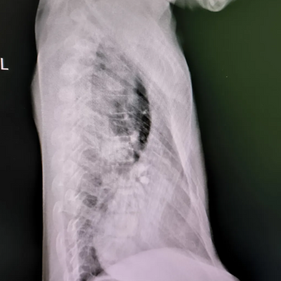

The patient's anterior chest wall exhibits a severe depression, with the deepest part of the depression extending beyond the anterior edge of the spine and sinking into one side of the chest cavity. The heart is severely compressed and completely displaced to the left chest cavity. The Haller index is negative, indicating the most severe type of pectus excavatum.